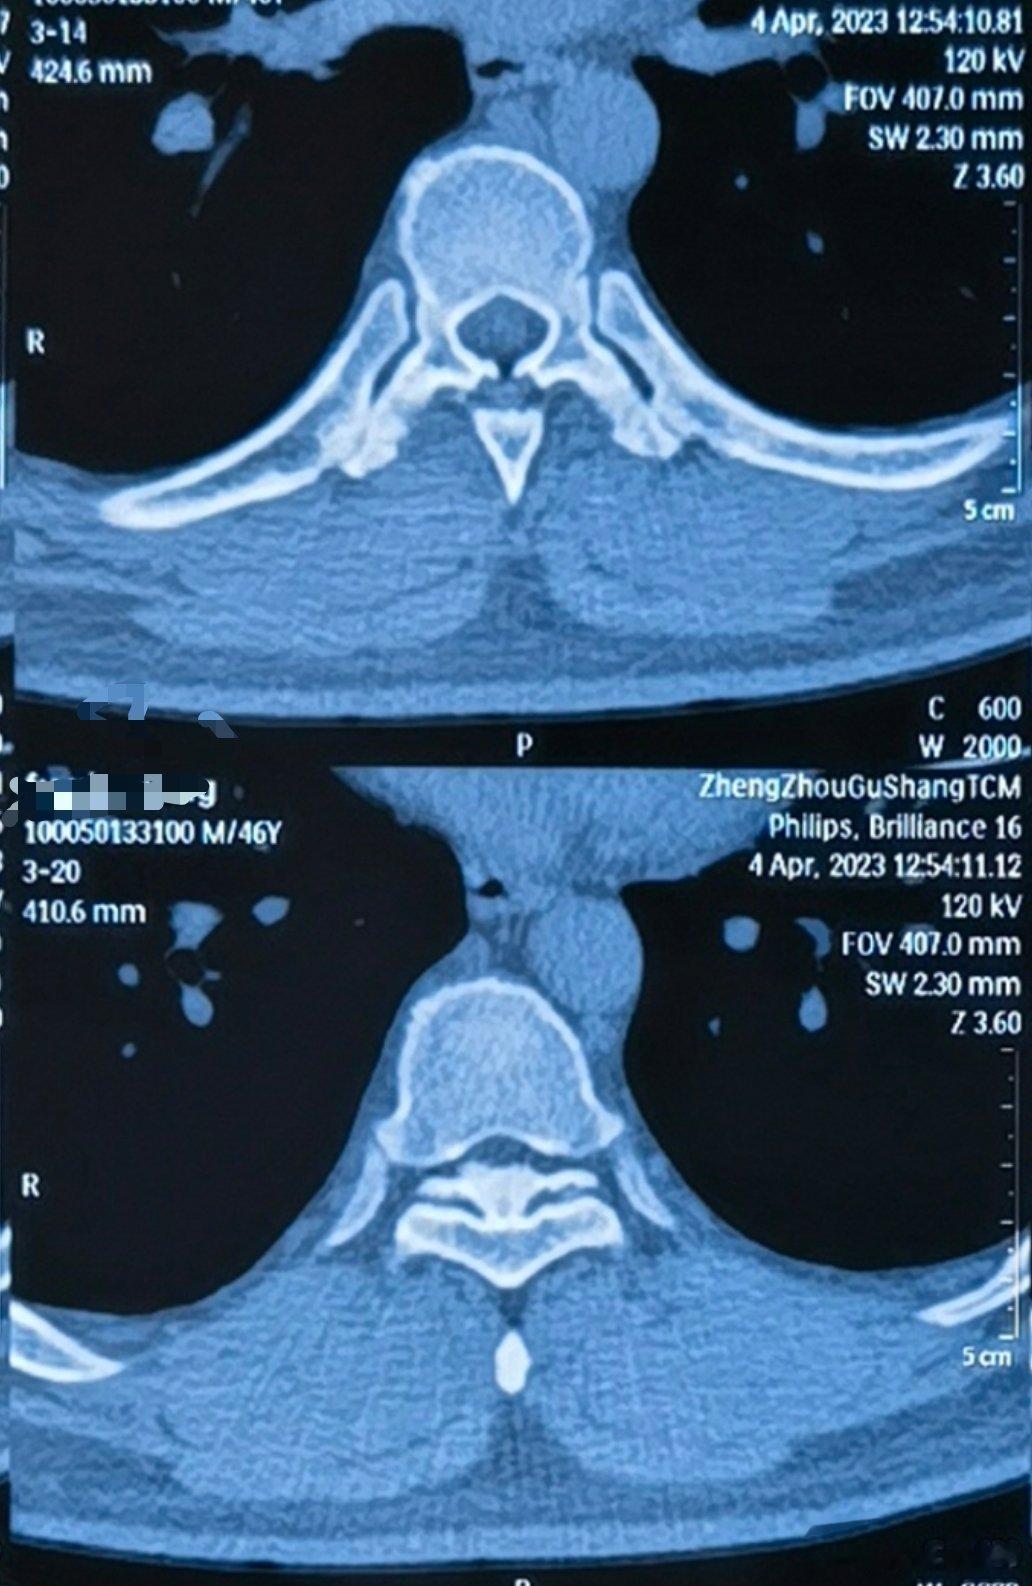

我有一个特殊的病人,40几岁一男的,特别倒霉。你看图里,这是胸椎黄韧带钙化,上面

2023-05-08 13:05